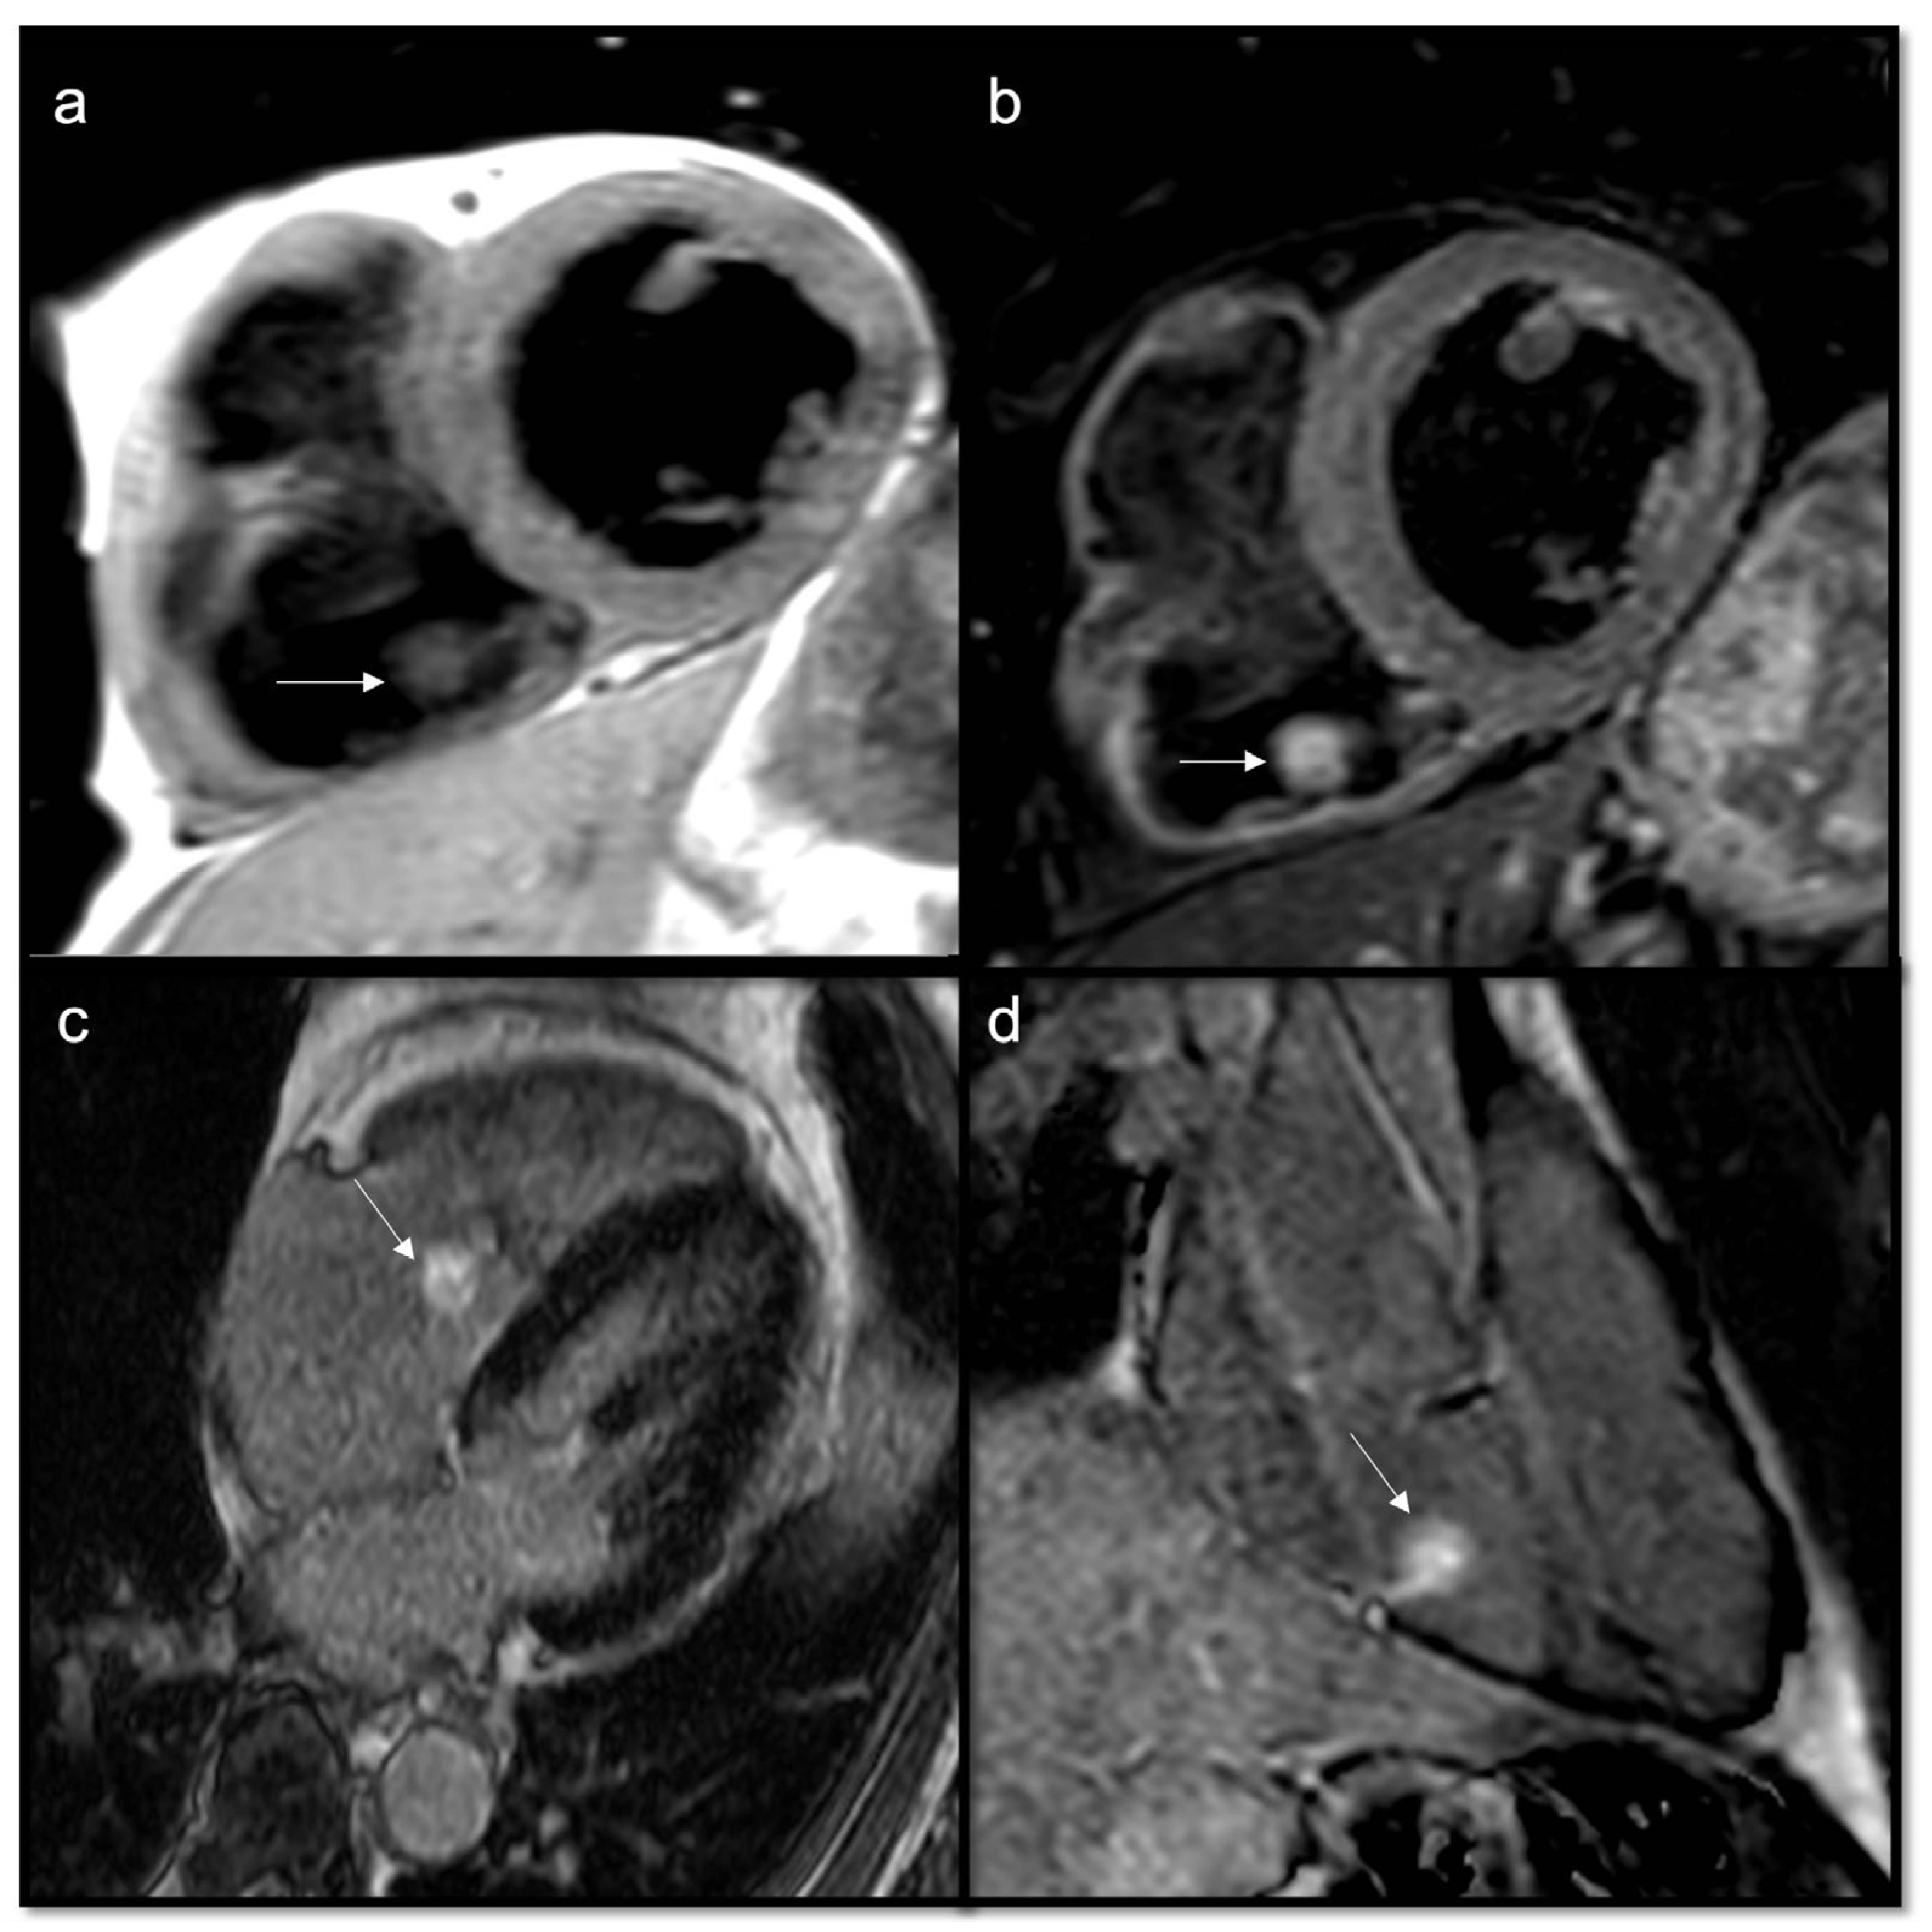

Figure 9.

Papillary fibroelastoma of the tricuspid valve (arrow) appears as a highly mobile, spherical pedunculate mass attached to the posterior tricuspid valve leaflet and on T1w images (a) it is homogeneous; no fatty content is found in T2w Fat Sat (b). LGE images demonstrate a hyperintense signal caused by fibroelastic tissue of the mass in 4CH and 2CH of the right ventricle (c,d). Approximately 80% occur concerning either the aortic or mitral valve, while tricuspid and pulmonary involvements are much rarer.